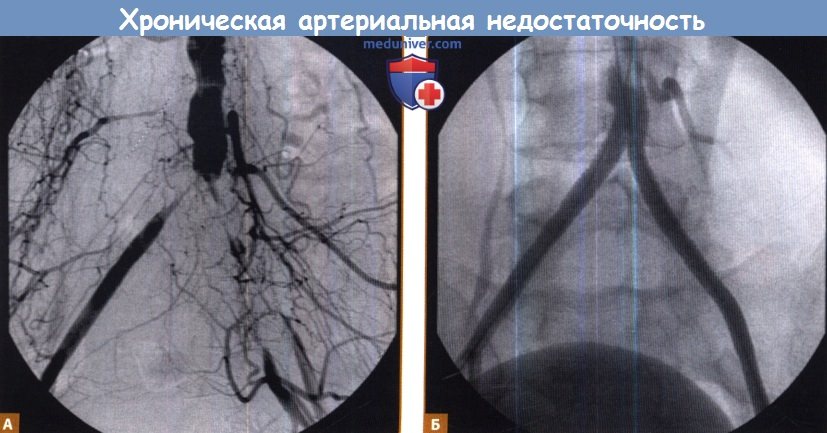

Изображения, связанные с атеросклерозом нижних конечностей и его лечением